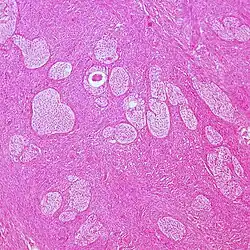

| Mucinous tumor | 15% | 8.8% | Benign mucinous tumors of the ovary consist of simple, nonstratified columnar epithelium with basally-located hyperchromatic nuclei and resemble gastric foveolar epithelium.[9] |

| |